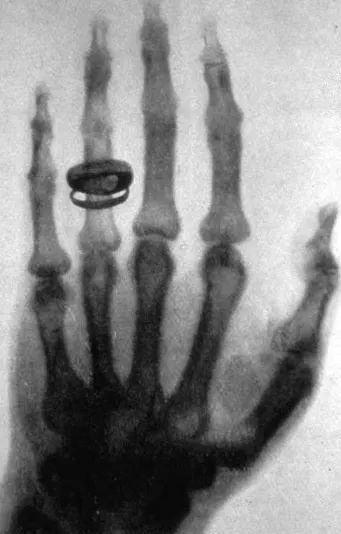

光學(xué)研究對(duì)自然科學(xué)的發(fā)展起到了非常大的促進(jìn)作用。回看歷史,第一個(gè)諾貝爾物理學(xué)獎(jiǎng)授予了倫琴,倫琴發(fā)現(xiàn)了X射線,揭開了20 世紀(jì)物理學(xué)的革命序幕,促進(jìn)了現(xiàn)代物理學(xué)的誕生。2002年諾貝爾物理學(xué)獎(jiǎng)仍然與X射線相關(guān),授予了對(duì)天體物理有開創(chuàng)性貢獻(xiàn)的宇宙X射線源的發(fā)現(xiàn),打開了宇宙新窗口。進(jìn)入21世紀(jì),多項(xiàng)諾貝爾獎(jiǎng)授予了光學(xué)領(lǐng)域,2017年的諾貝爾物理學(xué)獎(jiǎng)授予了引力波的探測研究,表彰獲獎(jiǎng)?wù)邆儤?gòu)思和設(shè)計(jì)了干涉儀引力波天文臺(tái),驗(yàn)證了愛因斯坦的百年預(yù)言,為人類探索宇宙配上了“耳朵”。2014年的諾貝爾物理學(xué)獎(jiǎng)授予了半導(dǎo)體照明研究,藍(lán)色發(fā)光二極管的發(fā)明使白光可以以新的方式被創(chuàng)造出來,人類可以擁有更加持久和高效的燈光替代光源,這也是與光學(xué)緊密相關(guān)的。2014年諾貝爾化學(xué)獎(jiǎng)同樣授予了光學(xué)研究領(lǐng)域,因光學(xué)顯微成像技術(shù)的最高分辨率一直無法超過光波波長的一半,被認(rèn)為是光學(xué)顯微鏡理論上的分辨率極限,而獲獎(jiǎng)?wù)邆儏s將超分辨熒光顯微技術(shù)的極限拓展到了納米量級(jí),一百多年沒有人能夠突破的極限被三位科學(xué)家成功地繞過,使得透視生命體分子的運(yùn)動(dòng)成為可能。2009年,諾貝爾物理學(xué)獎(jiǎng)被授予英國華裔科學(xué)家高錕及美國科學(xué)家威拉德·博伊爾和喬治·史密斯。高錕在“有關(guān)光在纖維中的傳輸以用于光學(xué)通信方面”取得了突破性成就。博伊爾和史密斯發(fā)明了半導(dǎo)體成像器件—電荷耦合器件(CCD)圖像傳感器,光纖通訊及CCD成像技術(shù)都與我們的日常生活息息相關(guān)。

圖3、威廉·康拉德·倫琴和X光照片